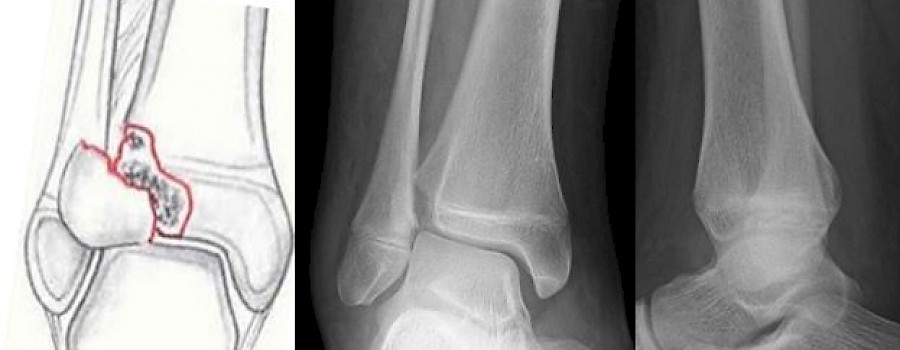

Die Übergangsfraktur ist eine besondere Frakturform der epiphysären Verletzungen zum Zeitpunkt des Wachstumsfugenverschlusses. Durch teilweise Verknöcherung der Wachstumsfuge entstehen spezifische Frakturmuster, die sich von der typischen Innenknöchelfraktur bei noch weit offenen Fugen unterscheiden.

Was ist auf unserem heutigen ominösen Röntgenbild abgebildet?